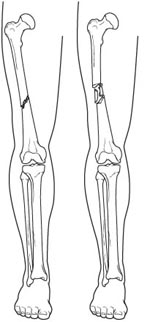

Types of femur fractures.(Left) An oblique, displaced fracture of the femur shaft.(Right) A comminuted fracture of the femur shaft.